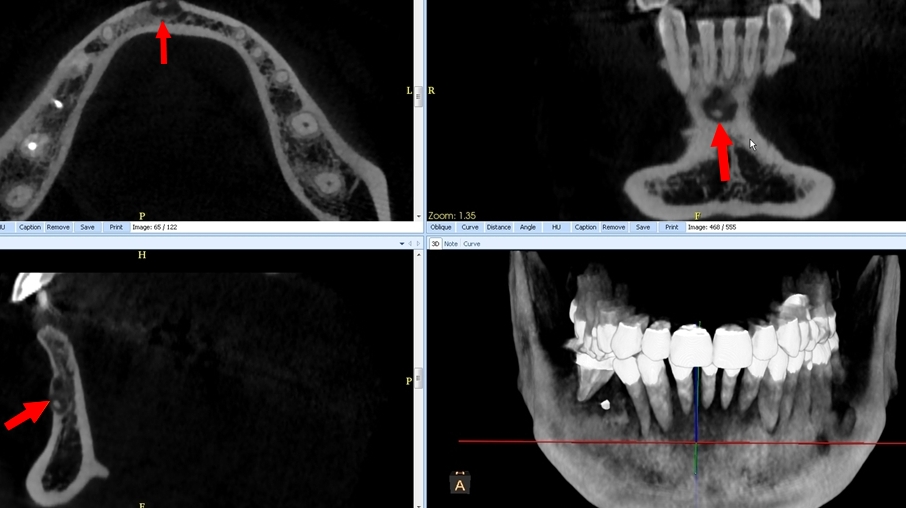

B. La dysplasie osseuse (ou cémento-osseuse) floride (Fig.4). Elle touche surtout la femme noire d’âge moyen, affectant les deux maxillaires de façon plus ou moins diffuse et symétrique, associant des lésions de grande taille à tous les stades, pouvant s’infecter et se compliquer d’ostéite.

C. Le diagnostic est : Dysplasie osseuse (anciennement cémento-osseuse) floride.

L’attitude à adopter est l’abstention thérapeutique. Les dents sont vivantes et doivent être considérées comme des dents saines, sauf complications infectieuses, comme pour tout patient.

Affections congénitales caractérisées par la production accrue de cément réalisant des lésions cémento-osseuses apicales non tumorales. Leur traitement est le plus conservateur possible et l’intervention réservée aux cas compliqués et/ou symptomatiques.

Leurs trois formes sont probablement les variantes d’un même processus lésionnel.